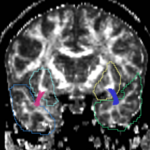

=====Cingulum=====

For the cingulum, the three different groups of tracts for each side (L,R) were combined for a single mean measure.

Cingulum

OUTPUT cing0.PNG OUTPUT cing1.PNG OUTPUT cing2.PNG OUTPUT cing3.PNG OUTPUT cing4.PNG OUTPUT cing5.PNG

OUTPUT cing6.PNG OUTPUT cing7.PNG OUTPUT cing8.PNG OUTPUT cing9.PNG OUTPUT cing10.PNG OUTPUT cing11.PNG